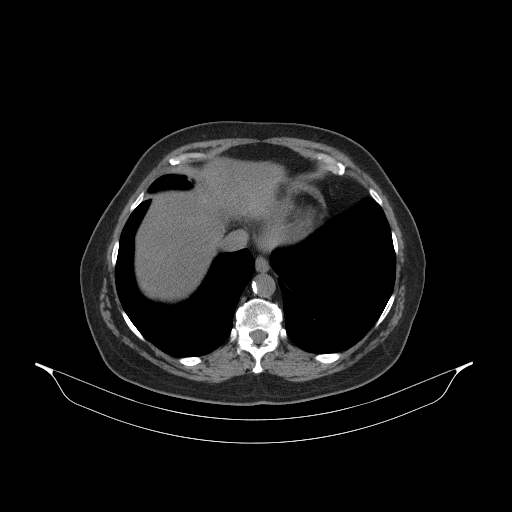

Original VENOUS CT scan

Full window (WL 1023.5, WW 4095 β†’ Low βˆ’1024, High +3071)

Actual HU range: [-160.0, 240.0]